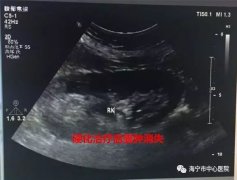

如果囊肿较小(直径小于5cm),无肾实质或肾盂明显受压,无感染、恶变,患高血压的人都不主张手术,可定期做B超随访观察。

如果囊肿较大(直径大于5cm)或有上述明显压迫肾脏、感染等表现,则应行手术治疗,手术包括:经B 超或CT引导下穿刺注射硬化剂、肾囊肿去除术,目前腹腔镜肾囊肿去除术因创伤小、恢复快,已成为肾囊肿手术的首选术式。